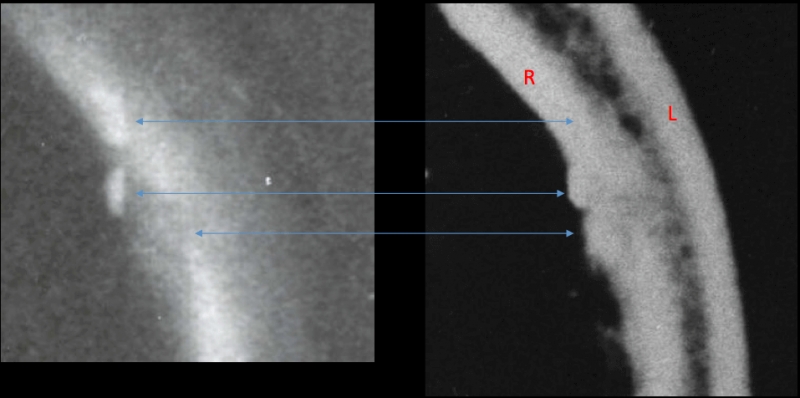

Biological Map in JFK’s Neck Points to South Knoll

If the bullet wound in John Kennedy’s throat was an entrance, then of course the shot came from the front. But that small hole in the skin, when viewed in relation to the neck’s internal damage, can tell you even more about where that shot came from, writes Milicent Cranor.